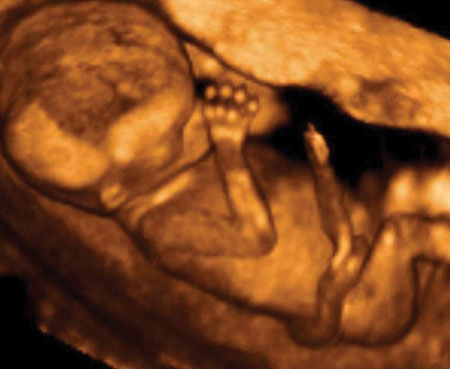

ToggleBu dönemde bebekte meydana gelen en önemli değişim ise artık bütün organlarının tamamlanmış olmasıdır. Saç tırnak gibi keratinimsi yapılar oluşmaya başlamıştır. Sindirim işlemleri de bu hafta oluşmaya başlamıştır. Bu dönemlerde bebekler fazlasıyla hareketli bir yapıya sahip olup ağız açıp kapama işlemlerini yaparlar. Bebekler bu zamanlarda parmaklarını da emmeye başlarlar.

12.Haftada ortalama bebek boyu 8 cm. ve ortalama ağırlık da 14 gramdır.

Bebeklere belirli testler uygulanırken onların ultrasonda oldukça garipseyebileceğiniz hareketler yapması da ilginizi çekebilir, ancak bu dönemde bu hareketler onlardan beklenen olası davranışlardandır.